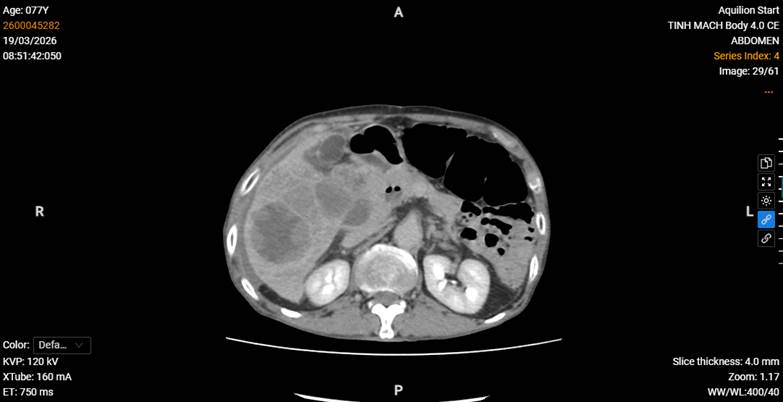

Xét nghiệm cận lâm sàng cho thấy tình trạng thiếu máu, rối loạn chức năng gan trên nền bệnh lý mạn tính. Hình ảnh chụp CT Scanner bụng có tiêm thuốc cản quang ghi nhận: gan có nhiều khối u phù hợp ung thư biểu mô tế bào gan, trong đó khối u lớn tại hạ phân thùy IV–V bị vỡ, gây chảy máu trong bao gan và một lượng dịch máu tự do trong khoang phúc mạc. Ngoài ra, phát hiện huyết khối không hoàn toàn tĩnh mạch chủ dưới và tĩnh mạch gan phải, giãn nhẹ đường mật trong gan vùng hạ phân thùy V, VI, cùng với giảm tưới máu nhu mô gan tại các phân thùy VI, VII.